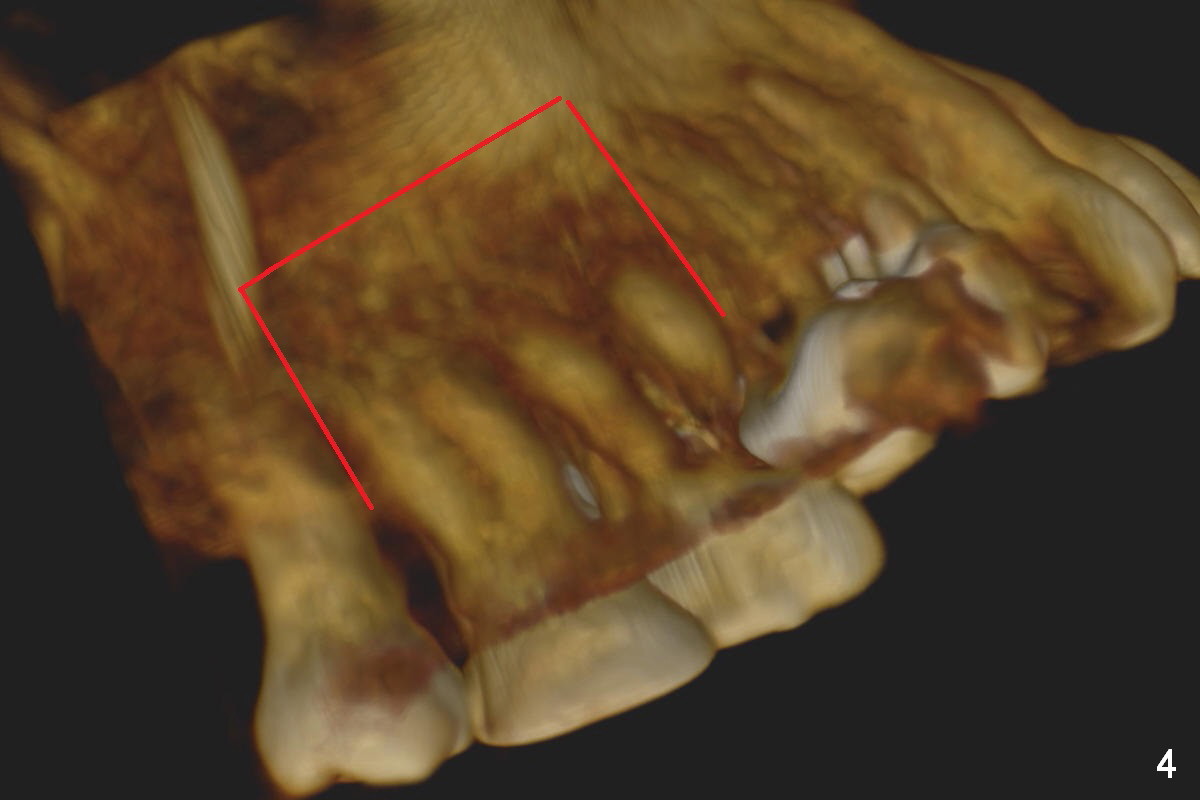

Orthodontic intrusion with mini-implants does not seem to work. When segmental brackets and bands are supplemented, the neighboring tooth (#14) becomes loose. CBCT 3 D and sagittal section show ~3 mm supraeruption of the teeth #2 and 3 (Fig.1,2). Diagnostic wax up demonstrates that the teeth #2 and 3 need to be intruded for 4 and 2 mm, respectively. Buccal gingival sulcus and anterior oblique incisions are shown in Fig.3 (red line). Osteotomy will be made with surgical fissure bur and chisels (Fig.4 red lines). The segment is down fractured (Fig.5 arrow). Apical bone is removed with acrylic bur and/surgical burs (Fig.6 cross lines). The segment is elevated and checked with a prefabricated splint out of diagnostic wax up. Insert a thicker orthodontic wire into brackets and bands buccally.